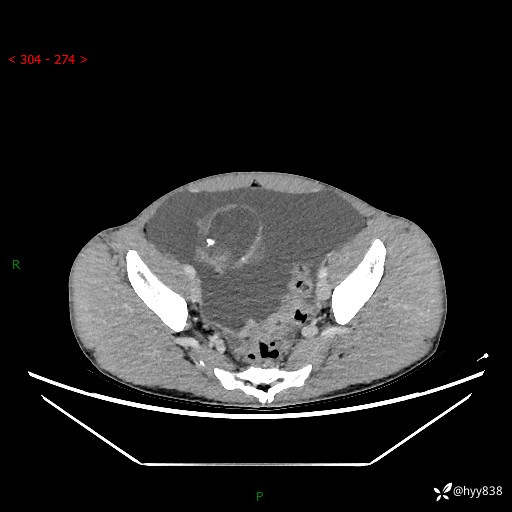

现病史:患者10天前无明显诱因出现腹部胀痛不适,无畏寒发热,无胸痛胸闷,无心慌气短,无恶心呕吐,无腹泻及黑便,无粘液血便及里急后重等症状,4天前在当地县人民医院就诊,行腹部CT示:下腹部占位性病变,腹腔及盆腔积液;今患者为求进一步诊治来我院治疗,门诊以“腹水”收治入院。 发病以来,精神饮食可,大小便正常,体重体力无明显变化。

腹部CT平扫+增强